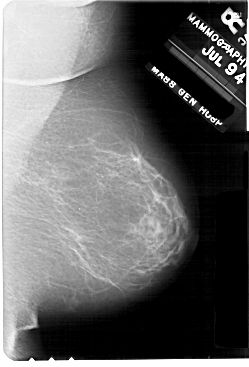

A_1707_1.RIGHT_CC

RIGHT_CC LINES 5491 PIXELS_PER_LINE 3106 BITS_PER_PIXEL 12 RESOLUTION 43.5 NON_OVERLAY